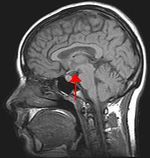

Biological psychology is the scientific study of the biological bases of behavior and mental states. Because all behaviour is controlled by the central nervous system, it is sensible to study how the brain functions in order to understand behaviour. This is the approach taken in behavioural neuroscience, cognitive neuroscience, and neuropsychology. Neuropsychology is the branch of psychology that aims to understand how the structure and function of the 'brain' relate to specific behavioural and psychological processes. Often neuropsychologists are employed as scientists to advance scientific or medical knowledge. Neuropsychology is particularly concerned with the understanding of brain injury in an attempt to work out normal psychological function.

The approach of cognitive neuroscience to studying the link between brain and behaviour is to use neuroimaging tools, such as to observe which areas of the brain are active during a particular task.